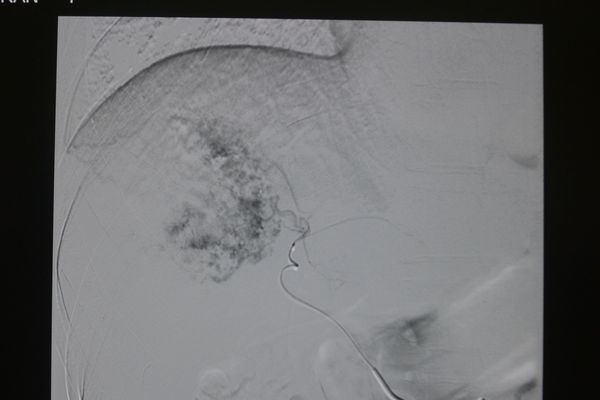

典型病例:

2013年12月5日,我院肿瘤科为1名巨大肝血管瘤患者成功实施了DSA下超选肝动脉栓塞治疗。该患者为男性,41岁,发现肝血管瘤3年余,因近期瘤体增大并出现肝区不适就诊。因瘤体较大,外科切除出血风险较高,故选择肝动脉栓塞术治疗。治疗后症状明显缓解出院。